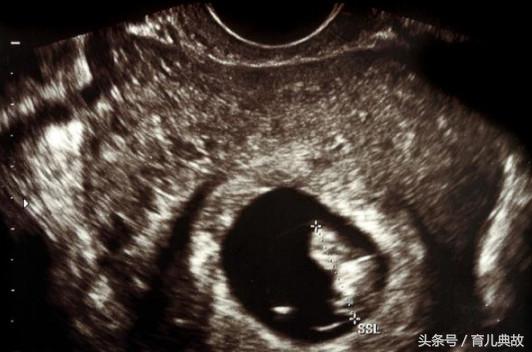

不知道是太紧张的缘故,怀孕;两个月就感觉腹部有些轻微隆起,可按常理来说不可能的啊,以为胎儿有啥问题赶紧去医院检查,不过还好只是孕囊偏大两周,这样的结果还是让人开心的!

直到怀孕三个月去建卡,第一次产检,有孩子后小姚和老公只祈求宝宝健康就好却没想到宝宝却给了这么大的一个惊喜!医生在做B超的时候说有两个宝宝,胎心胎芽都有。